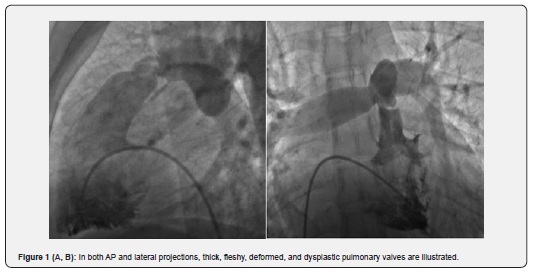

In the unsuccessful group (8 patients), who at 1-year follow-up had higher RVSP (117.5mmHg), dramatically more infundibular hypertrophy, dysplastic valve, and astounding immobile valve were illustrated, so eventually all of them underwent surgical procedure. Previous studies have shown that because of impaired mobility of the dysplastic pulmonary valve, surgery is the preferred treatment [10]. In our study, among the 8 failed procedures, 5 (4.5%) had dysplastic pulmonary valves (Figure 1A & B); three of eight patients had immobile leaflet but not dysplastic valves combined with severe infundibular hypertrophy (Figure 2A, B) who underwent PV commissurotomy and infundibular resection.